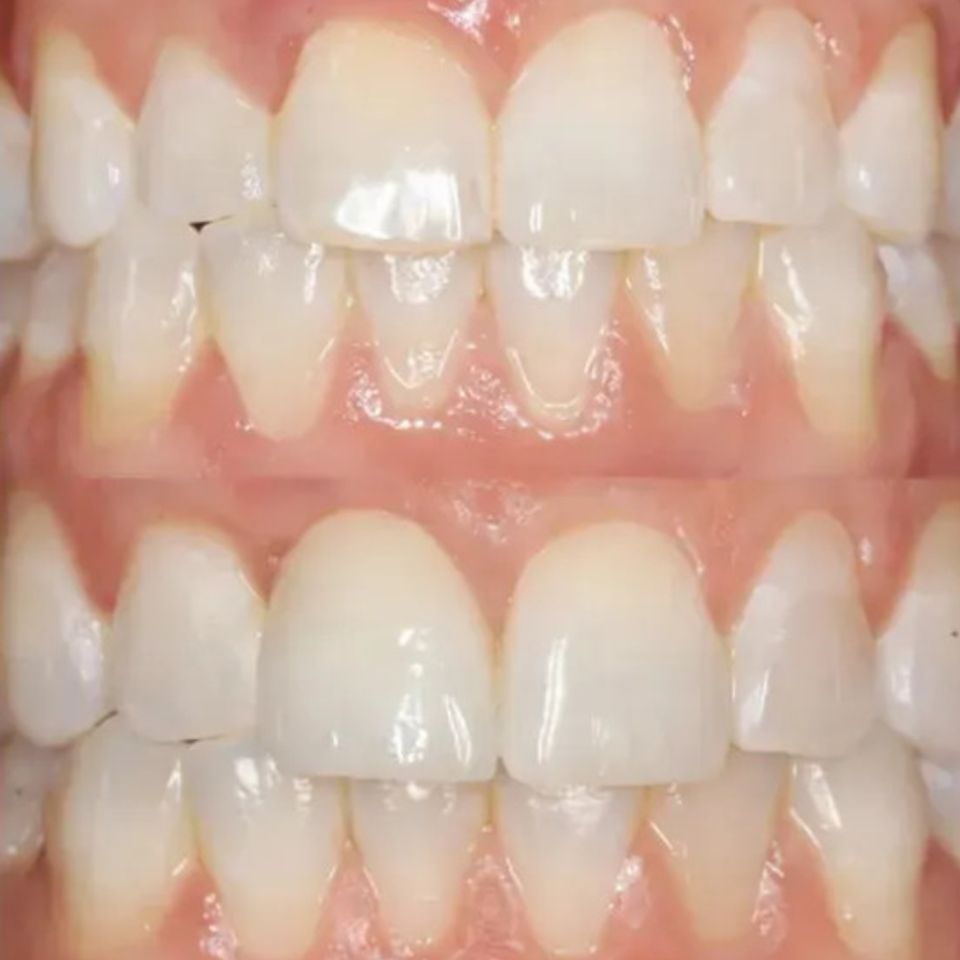

At our practice, we recently helped a patient restore their smile after experiencing a complex dental issue involving a periodontal infection and a root fracture. To fully restore both health and aesthetics, we recommended a comprehensive implant-based solution.

• Implant Placement with Soft Tissue Grafting to ensure long-term stability and natural-looking gum contours

• Final Implant-Supported Crown, custom-designed for strength, beauty, and seamless integration

We are extremely proud of the final result, and most importantly, our patient is now enjoying a healthy, confident smile once again.